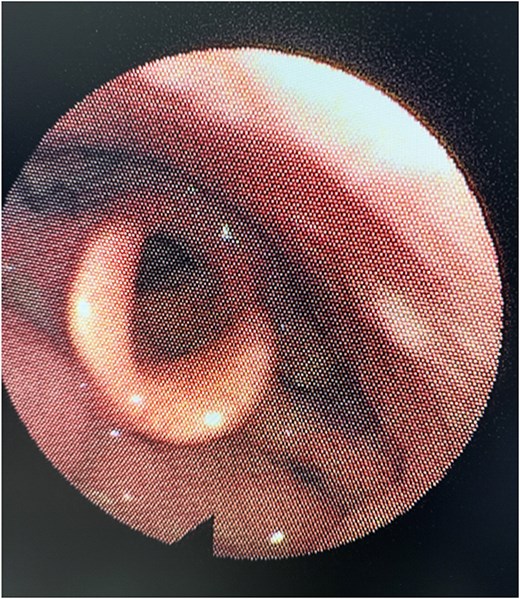

Flexible nasal endoscopy revealed a congested laryngeal mucosa with normal vocal cord movement and appearance. The epiglottis was tubal-shaped with a left aryepiglottic fold mass that was rounded in shape with normal overlying mucosa (Fig. 1). The remainder of the laryngeal examination was unremarkable.

Pre-operative nasal endoscopy showing a rounded, submucosal mass (L) in the left aryepiglottic fold. The epiglottis (E) appears normal with no signs of inflammation or distortion. Note the smooth contour of the lesion with intact overlying mucosa.